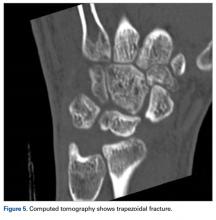

A fit and healthy 30-year-old male software professional fell down stairs, landed on his nondominant right hand, and sustained a high-energy wrist injury. The patient also sustained a concussion, without focal neurologic deficit, and was unable to recall the exact mechanism of the wrist injury (there were no other witnesses). Radiographs of the right wrist in the emergency department showed only a nondisplaced fracture of the neck of the second, third, fourth, and fifth metacarpals and a nondisplaced fracture of the radial styloid.

Later, however, the hand surgery team evaluated the radiograph as well as computed tomography (CT) scans and found a translunate, transradial, transtriquetral, transtrapezoid perilunate dislocation of the wrist with multiple metacarpal neck fractures ( Figures 1-5 ).The next day, with the patient under general anesthesia, an attempt to reduce the perilunate dislocation by manipulation was unsuccessful. Open reduction and internal fixation (ORIF) were performed through a dorsal approach; the perilunate dislocation was reduced and stabilized with lunocapitate 1.2-mm Kirschner wire (K-wire). The scapholunate and lunotriquetral ligaments were found to be intact, and the significantly displaced triquetral fracture was treated with internal fixation involving 2 minifragment screws ( Figure 6 ).

Perilunate injuries have been missed in busy emergency departments and orthopedic practices. An estimated 25% of such injuries can be missed on initial presentation. 8 In the present case, fracture of the radial styloid provided a clue to possible more complex carpal injuries involving the scaphoid, lunate, or scapholunate ligament, as Graham 4 suggested with the concept of the “transverse pattern” of force transmission. In this case as well, the injury was initially missed, and its extent became evident only with CT. Therefore, emergency teams should have a very low threshold for suspecting and evaluating high-energy wrist injuries.